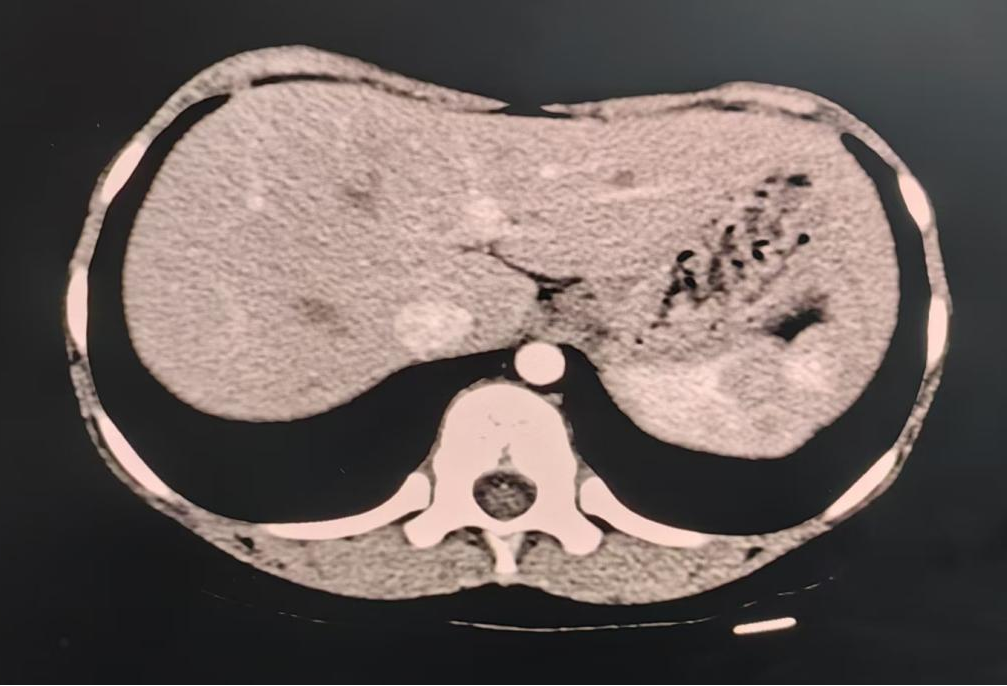

腹部增强CT:獭尾肝,余腹部CT平扫及增强未见明显异常。

图1. 腹部增强CT,獭尾肝表现